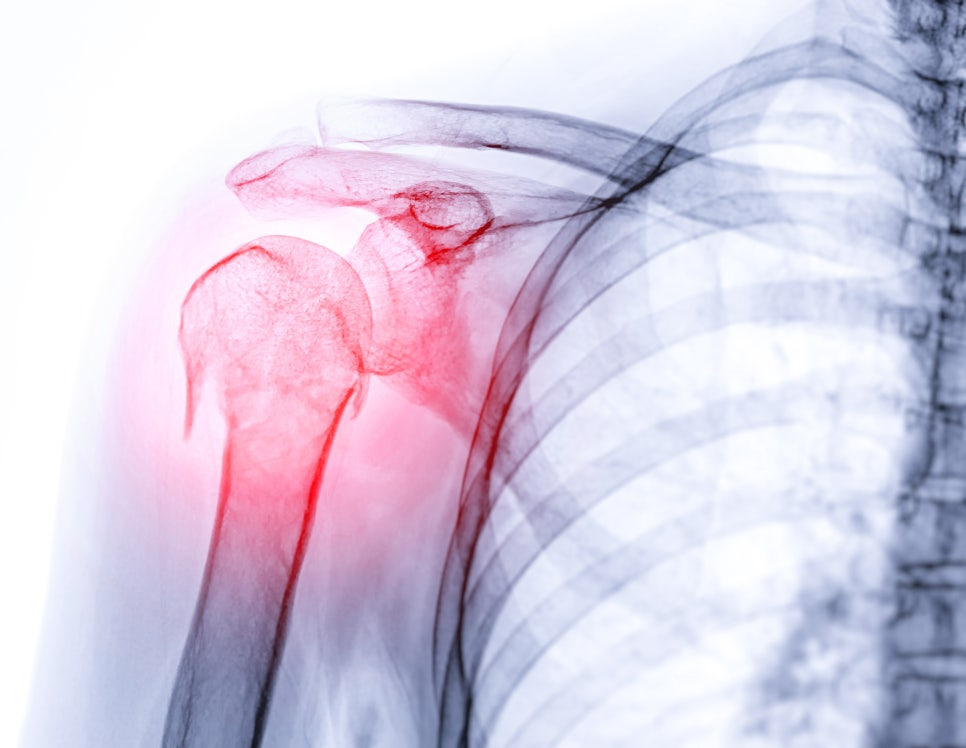

🟣 X-ray 촬영: 뼈 구조 이상이나 관절 간격 확인